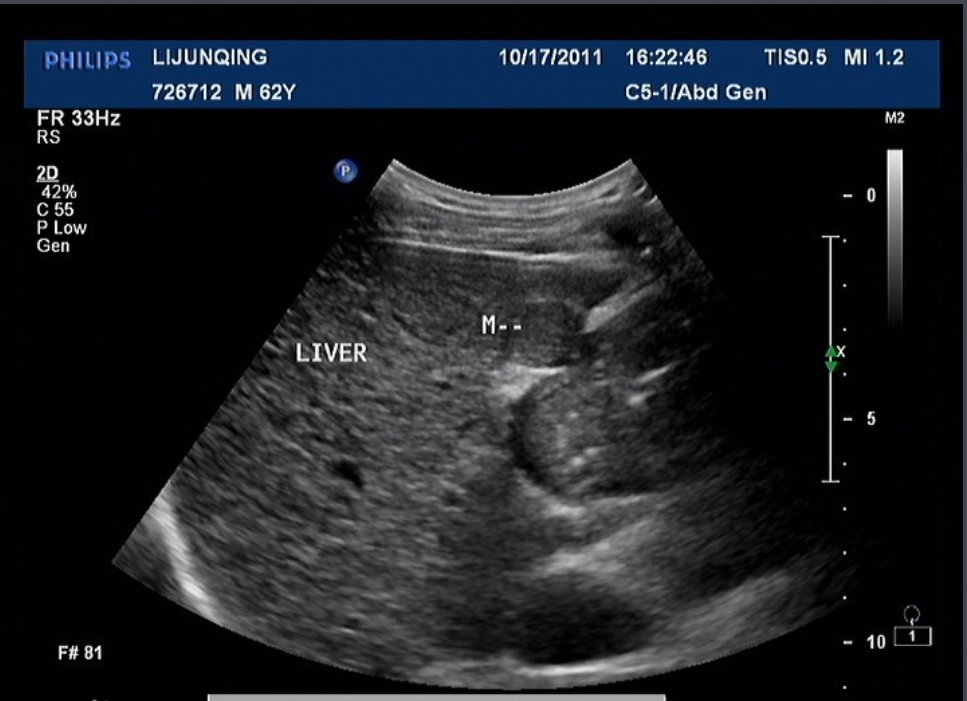

超声造影(Ultrasonic Contrast)又称声学造影(Acoustic Contrast),是利用造影剂使后散射回声增强,明显提高超声诊断的分辨力、敏感性和特异性的技术。

随着仪器性能的改进和新型声学造影剂的出现超声造影已能有效的增强心肌、肝、肾、脑等实质性器官的二维超声影像和血流多普勒信号,反映和观察正常组织和病变组织的血流灌注情况,已成为超声诊断的一个十分重要和很有前途的发展方向。

超声造影是通过造影剂来增强血液的背向散射,使血流清楚显示,从而达到对某些疾病进行鉴别诊断目的的一种技术。由于在血液中的造影剂回声比心壁更均匀,而且造影剂是随血液流动的,不易产生伪像。